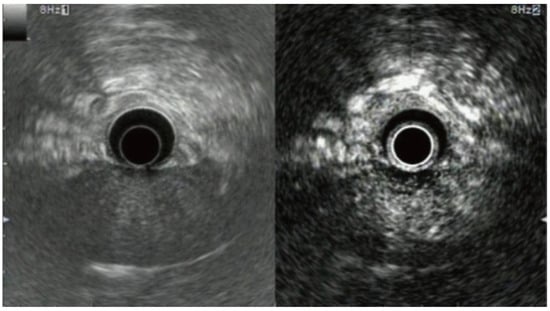

3. Conventional (Radial and Linear) Endoscopic Ultrasound

4. Miniature Probe Endoscopic Ultrasound